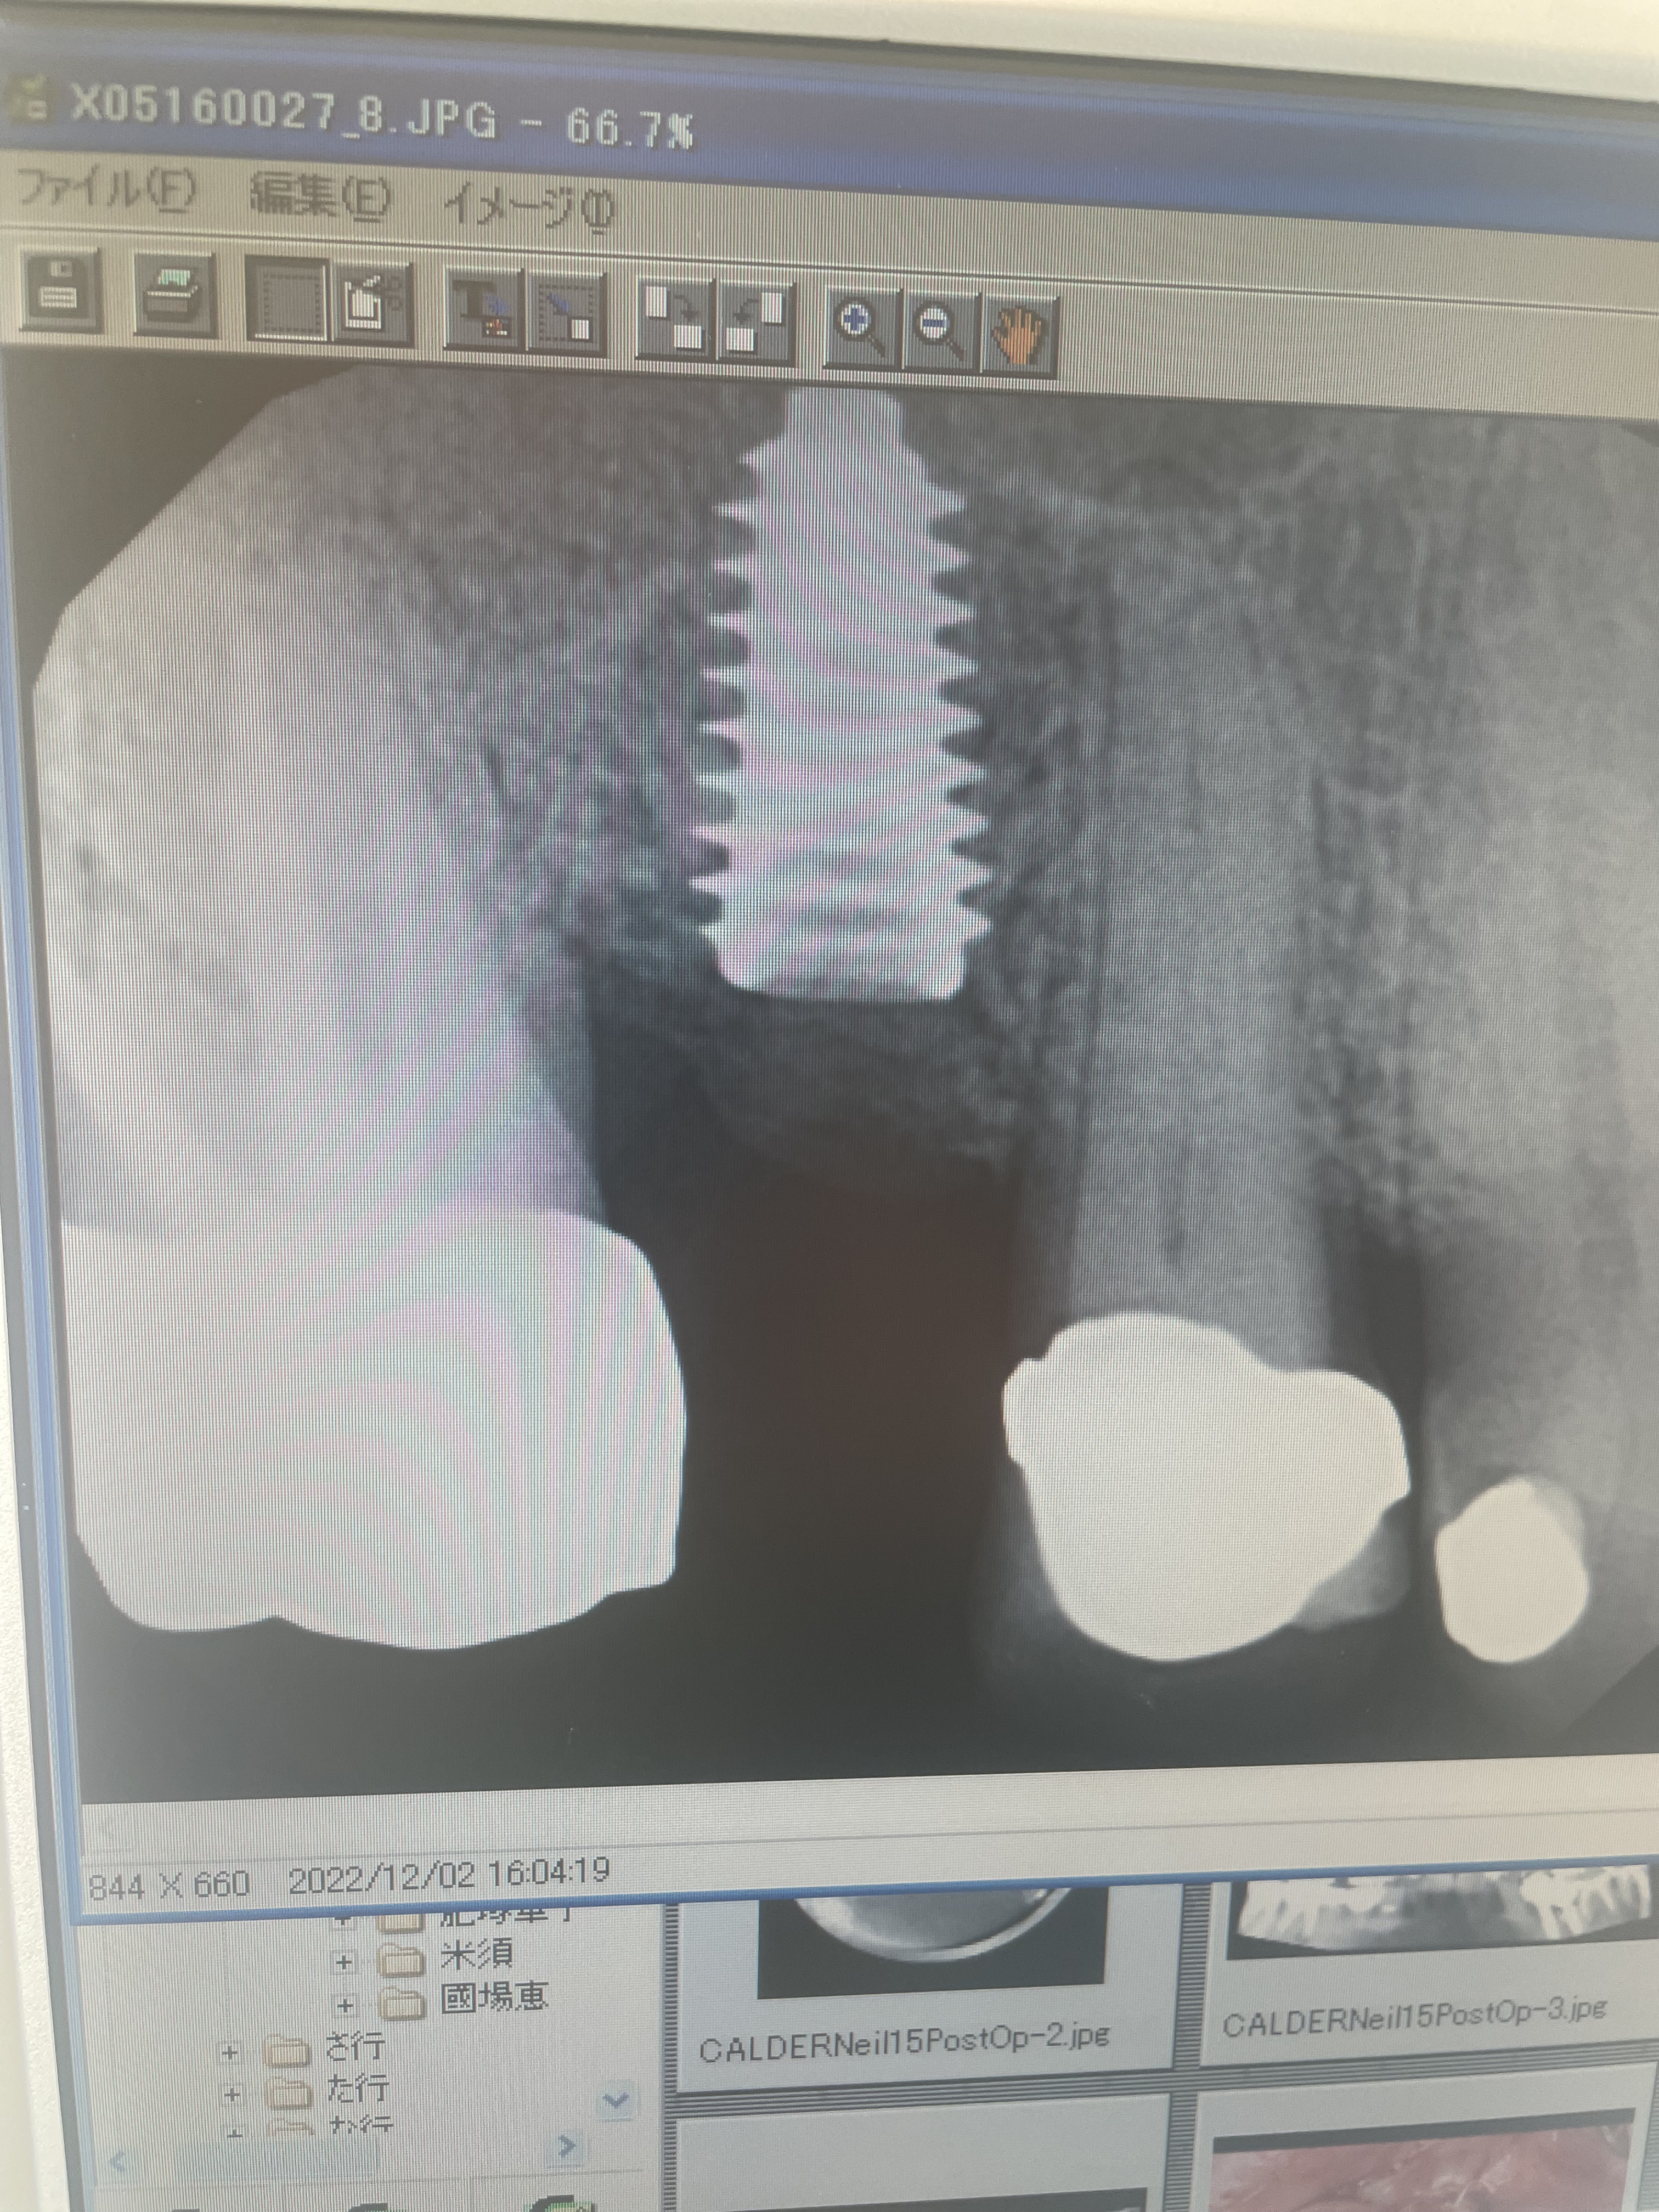

The time has come for another dental implant!

It is not much fun but passes the time. There are several more procedures before the whole thing is finished.